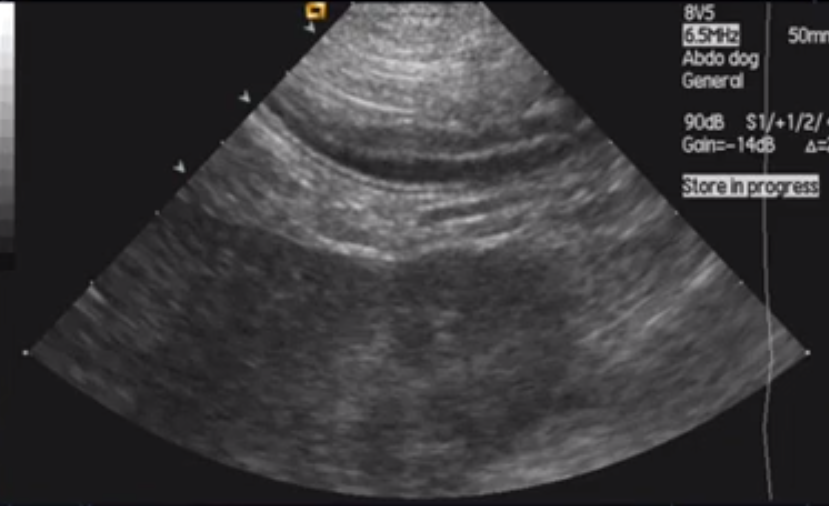

What does this image show?

Descending duodenum. Whiter (hyperechoic or more echogenic) line = R limb of pancreas